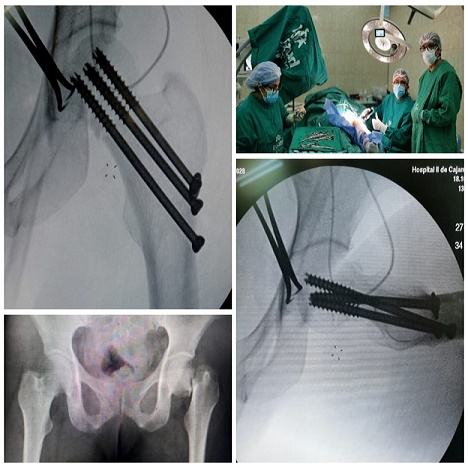

Dr. Elberth Tafur Sarmiento

Soy médico especialista en Traumatología y Ortopedia con más de 10 años de experiencia en el diagnóstico y tratamiento traumatológico. He obtenido una mejoría del 90% de mis pacientes, quienes le han dado un nuevo rumbo a su vida. Trabajo con dedicación, responsabilidad y mucha empatía para comprender a quienes solicitan mi ayuda.

Deseo replicar los resultados en el departamento de Traumatología del Hospital Regional de Cajamarca, Entidad actual de trabajo.